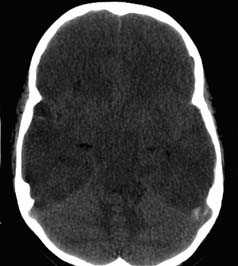

е) Диффузное аксональное повреждение (ДАП). ДАП представляет собой патологическое повреждение аксонов в результате травмы по механизму ускорения/замедления или вращения. Типичные локализации ДАП находятся на границе серого и белого вещества, в мозолистом теле, дорсолатеральном отделе ствола мозга, своде, базальных ядрах и внутренней капсуле.

Ключевые данные визуализации:

- При легком ДАП данные КТ часто нормальные.

- При КТ может быть выявлен умеренный отек мозга или микрокровоизлияния (20-50%) в местах повреждения или очаговое поражение (10%).

- При нормальной КТ у пациента с неврологическими нарушениями необходимо выполнение МРТ.

- МРТ более чувствительна, чем КТ в выявлении ДАП, которое лучше визуализируются на Т2-взвешенных и FLAIR изображениях в виде множественных четких гиперинтенсивных областей в белом веществе